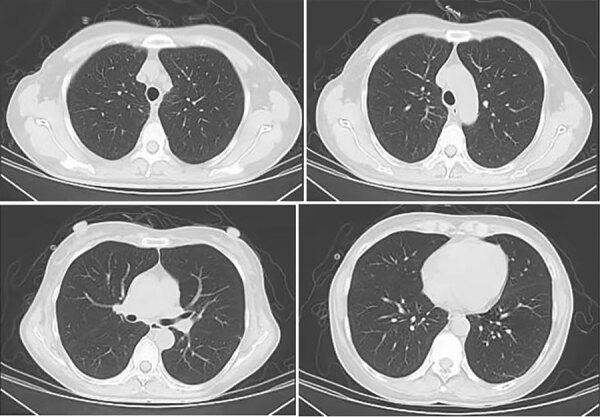

Pneumocystis jirovecii pneumonia is an opportunistic infection that affects HIV-infected and immunocompromised persons and rarely affects immunocompetent patients. However, after the advent of the COVID-19 pandemic, some COVID-19 patients without immunocompromise or HIV were infected with P. jirovecii. Clinical manifestations were atypical, easily misdiagnosed, and rapidly progressive, and the prognosis was poor.

肺孢子菌肺炎是一种机会性感染,影响 HIV 感染者和免疫功能低下者,很少影响免疫功能正常的患者。然而,在 COVID-19 大流行出现后,一些没有免疫抑制或 HIV 的 COVID-19 患者感染了肺孢子菌。临床表现不典型,容易误诊,病情进展迅速,预后不良。